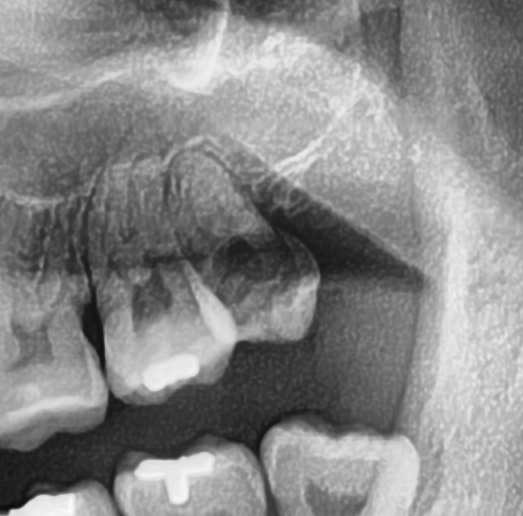

続けてパノラマ写真を撮影してみると、左上の親知らずは手前の歯と並んでまっすぐ生えているのが確認できました。

今回は上顎洞から近い距離にありますが、抜歯は可能と診断されました。